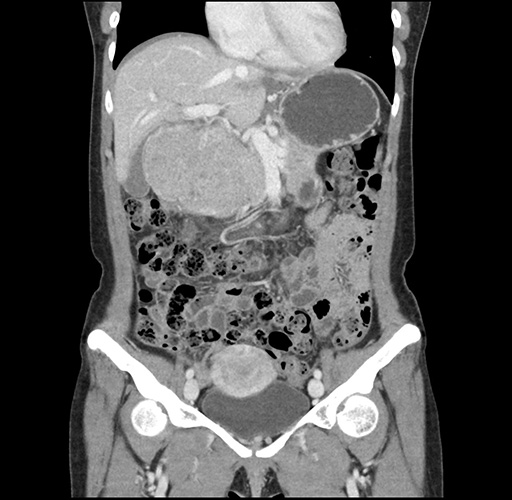

Imaging Analysis

Look through the patient's CT scan to identify any areas of concern for the necessary procedure.

Based on your CT findings, which issue(s) would give reason for "planned slowing down moment(s)" in this case?

Considering a standard left lateral sectionectomy procedure, what step(s) of the operation would you do differently in this case ?